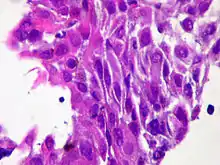

| Micrograph of squamous-cell carcinoma (H&E stain) | |

Squamous epithelial cells are not found in normal thyroid, thus the origin of SCT is not clear. However, it might be a derived from the embryonic remnants such as thyroglossal duct or branchial clefts. Often SCT is diagnosed in one of the thyroid lobes, but not in the pyramidal lobe. Another possible way of SCT development can be through the squamous metaplasia of cells. However, that theory is also controversial, since the Hashimoto's thyroiditis and chronic lymphocytic thyroiditis (neoplasms to be showed squamous metaplasia) are not associated with SCT. Primary STC is usually diagnosed in both lobes of thyroid gland. The histopathology of STC shows a squamous differentiation of tumor cells.